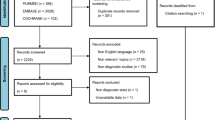

We conducted a cross-sectional observational study in the Renal ICU of the Parma University Hospital. Procedures were performed in accordance to the Helsinki declaration. Informed consent was obtained from patients or their next of kin. The study was approved by the Local Ethics Committee Area Vasta Emilia Nord (AVEN). Adult patients with a diagnosis of AKI on the basis of the KDIGO criteria [17] consecutively admitted from March 15, 2017 to March 15, 2018, and in whom CT scan was performed for any medical reason, were eligible. We used the STARD checklist when writing our report [18].

Thirty-four patients were eligible for the study. We enrolled 30 critically ill patients (17 males) with AKI, and we obtained 233 coupled measurements (1 patient had all his 4 proximal measurements excluded because the CT image was obtained on the wrong place, 1 patient was morbidly obese and his proximal VI muscle in both legs were not visible, and in 1 patient the image obtained of his proximal VI muscle on the right leg had an artifact that did not allow for a measurement). Four patients were excluded because CT scan images were not available due to technical or clinical problems. Patients were studied within 5 days (range 1–19) of the diagnosis pf AKI. The mean age of the cohort was 70 (± 13.6) years. Clinical and demographic data are shown in Table 1. The average APACHE II score was 21 (± 6); the median SOFA score was 7 (2–16). The majority of patients (17/30, 57%) had chronic kidney disease (CKD) prior to the ICU admission (AKI on CKD). Sixty percent of patients (18/30) underwent renal replacement therapy (RRT) within the first 24 h after ICU admission. Sixty-seven percent of all patients were oliguric and 27% were septic. Two hundred thirty-three couples of measurements were analyzed.